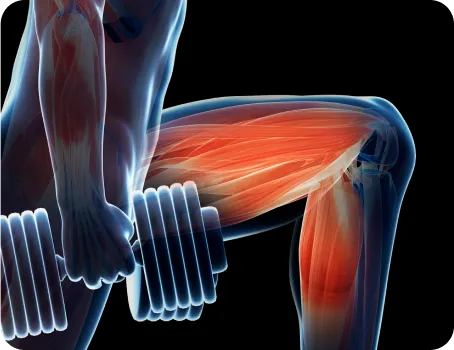

당당 도수치료는 겉과 속을 같이 치료합니다.

뼈뿐만 아니라 근육의 불균형까지 함께 보고,

재발 방지를 위해 본인도 몰랐던 보행 패턴까지 바꿉니다.

스포츠 재활 도수치료

스포츠 재활 전문 물리치료사의 정확한

근력 측정과 기능적 움직임 평가를 통해

통증을 치료하고 근력과 관절 가동범위를 회복하여

치료의 만족도를 높입니다.